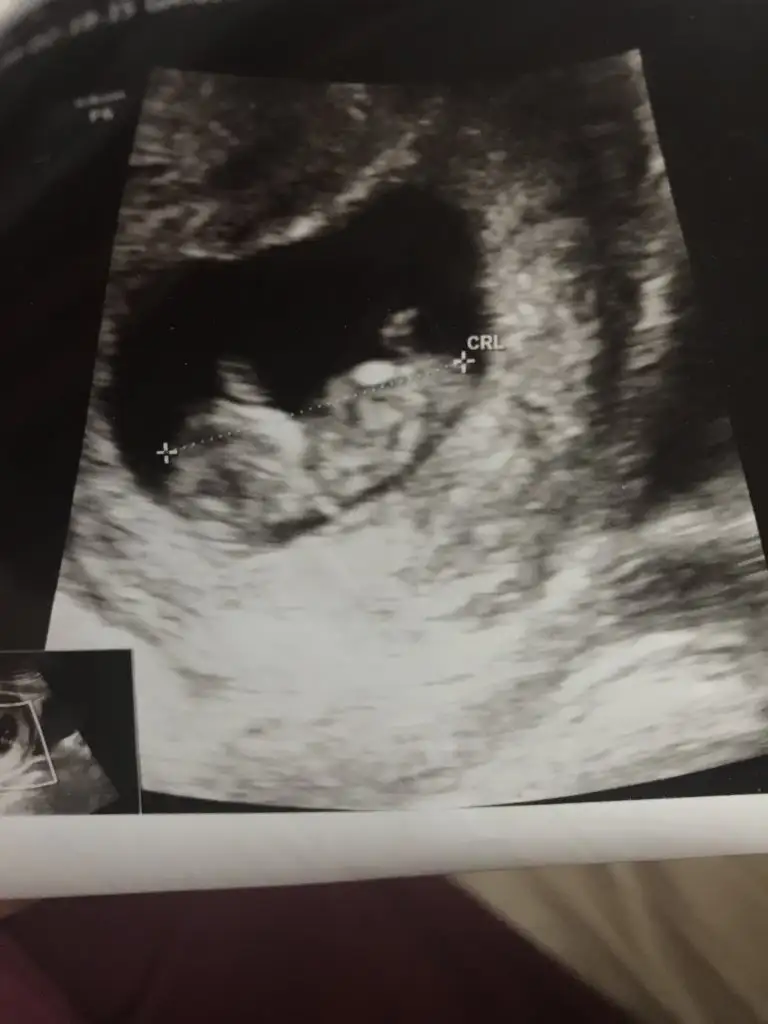

Kız sanki emin olamadım başka usgde paylaşınKızlar tahminde bulunabilirmisiniz ikiz bebekler 12 hafta 1 gunlikler

rBu kadar usg görüntüleri var malesef

9+3 haftada nub tahmini olmuyor nub için 11 yada 12 yada 13 haftaları paylaşınelimdeki tüm usg görüntüleri bunlaryeterli olur mu ki tahmin için